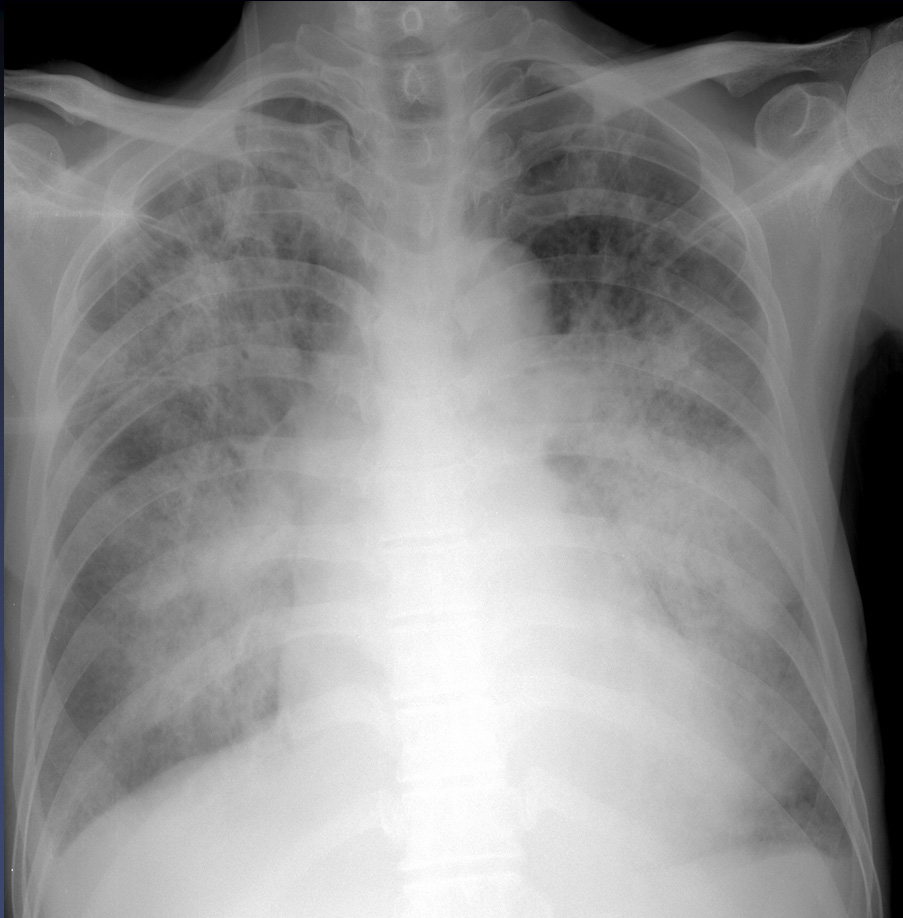

50yr / F, C.C: Atypical chest pain (onset; 6 MA)

Eun Ju Chun, Seoul National University Bundang Hospital

HIT : 10737